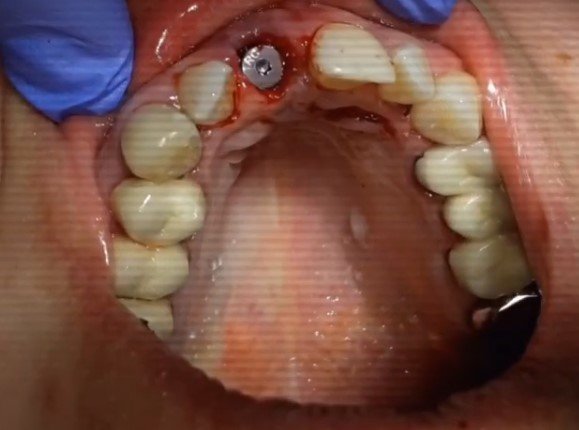

All-on-4 («все на четырех») - прогрессивный протокол имплантации челюсти на 4 имплантах, применяющийся для протезирования зубного ряда при его значительных...

Фронтальные зубы как никогда важны для пациента! Конечно работа с передними зубами сложна и кропотлива! Требует особой тактики ведения. @dr.logvinov...